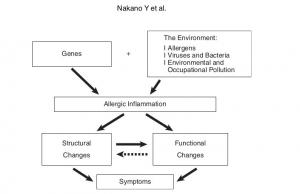

Radiological Approach to Asthma and COPD-The Role of Computed Tomography.